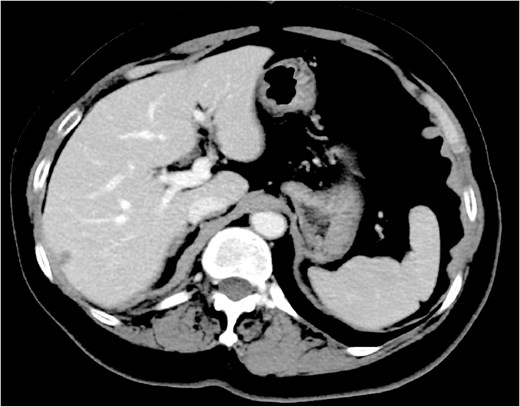

First-line treatment with docetaxel, trastuzumab, and pertuzumab administered every three weeks was initiated in June 20XX. Following six cycles (October 20XX), contrast-enhanced CT demonstrated a 52% reduction in the breast mass and complete resolution of the splenic lesion (Fig. 2). At re-evaluation in April 20XX + 1, the primary mass had shrunk by 59%, and the spleen remained clear. Maintenance dual anti-HER2 therapy is ongoing, and the patient remains progression-free at 22 months.

Effect of chemotherapy plus anti-HER2 therapy on splenic metastasis. Contrast-enhanced CT following six cycles of docetaxel, trastuzumab, and pertuzumab shows complete resolution of the splenic lesion.